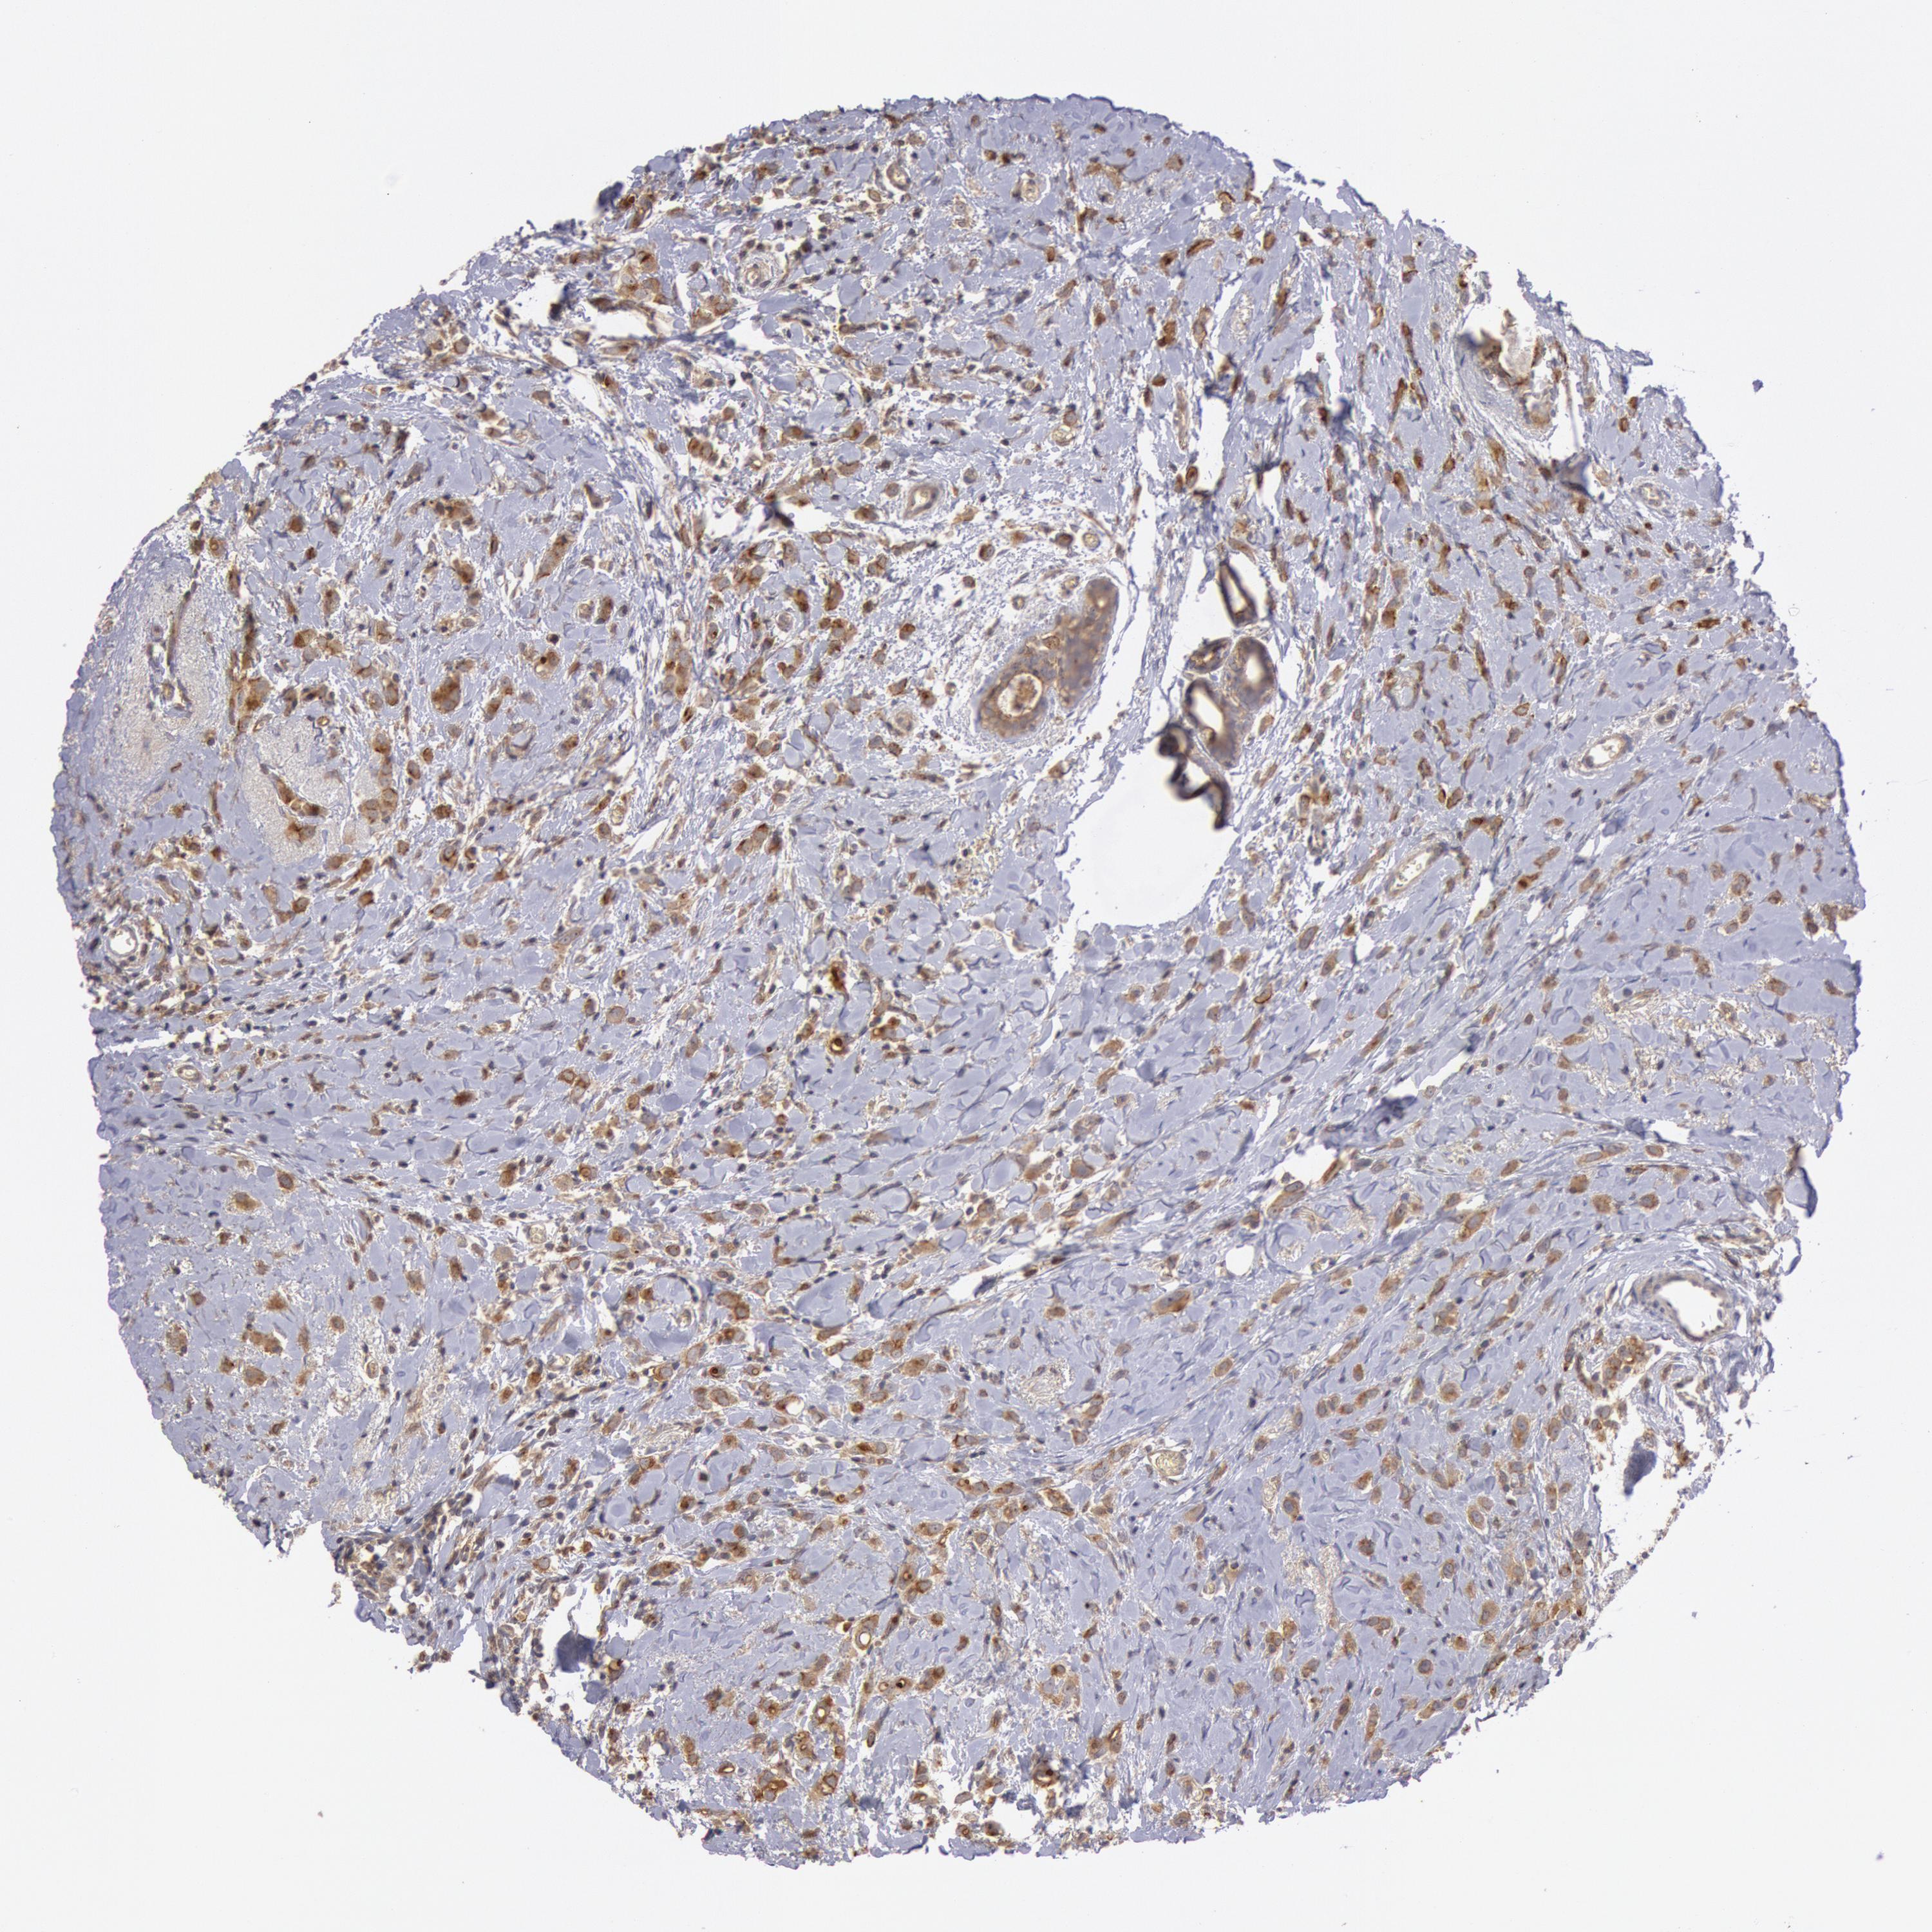

CANCER BREAST CANCER Show tissue menu

BRCA TCGA BRCA VALIDATION PROTEIN EXPRESSION